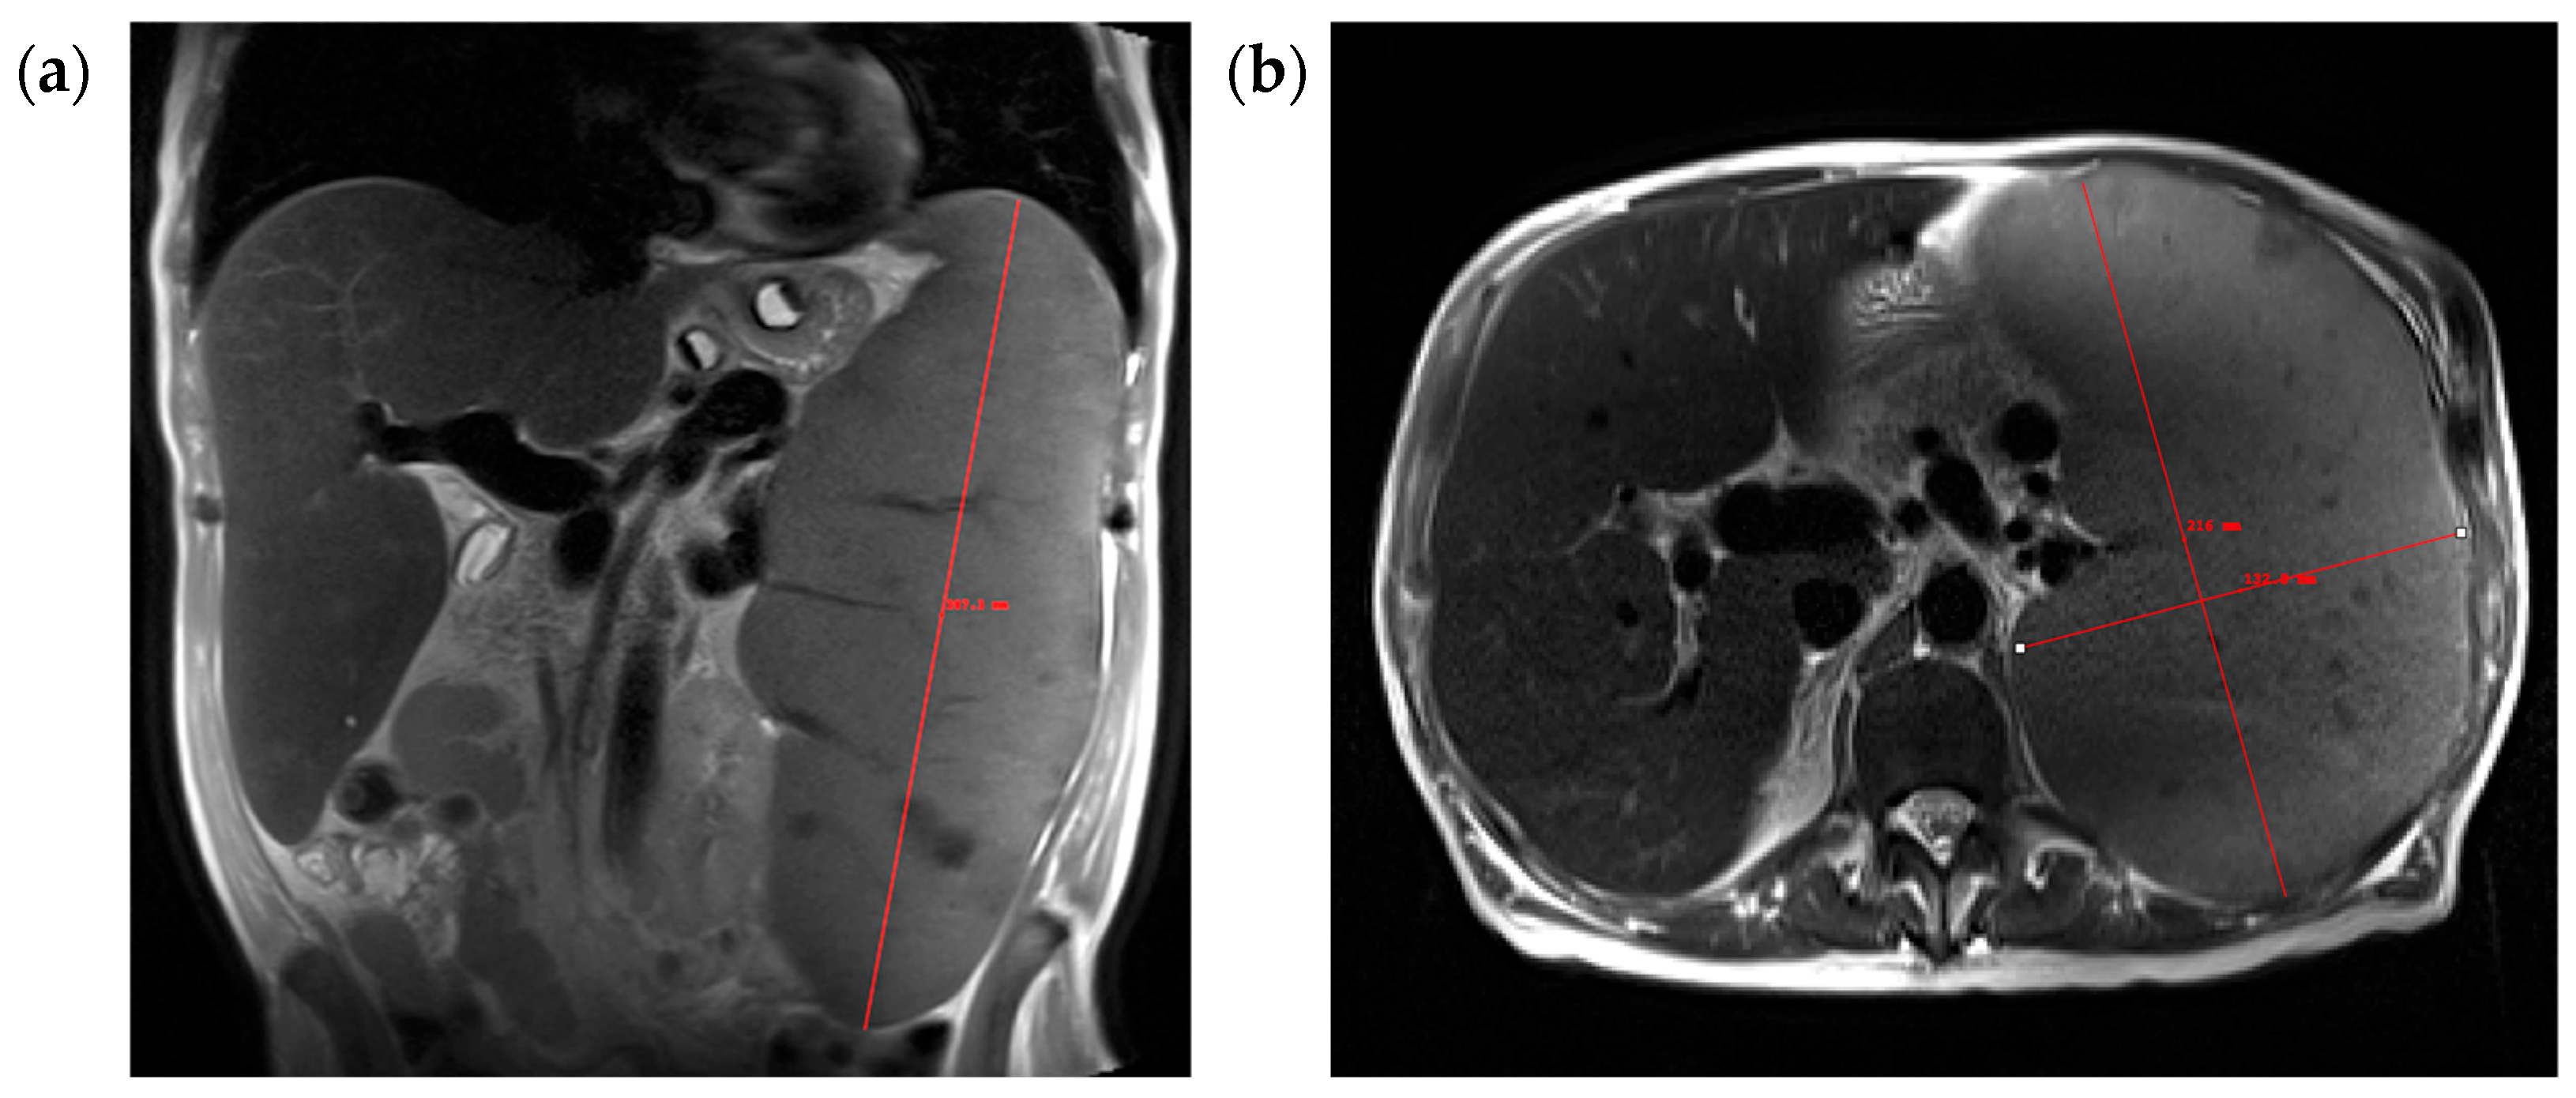

2.4. Spleen Volume Measurements